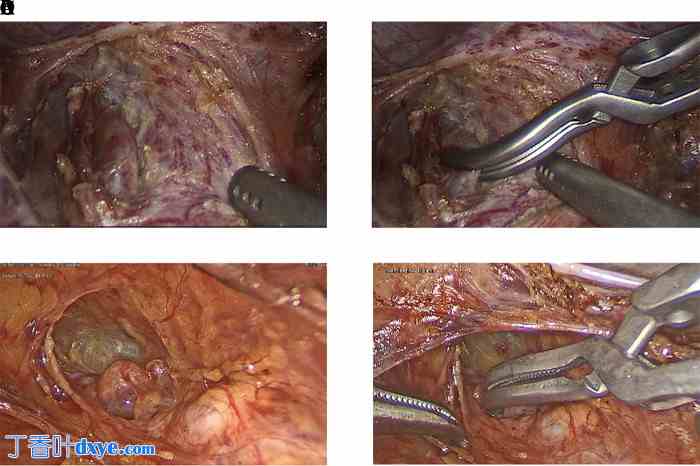

图2.

子宫动脉阻断。(A 和 B) 子宫下段中段。(C 和 D) 靠近脐动脉的侧位。